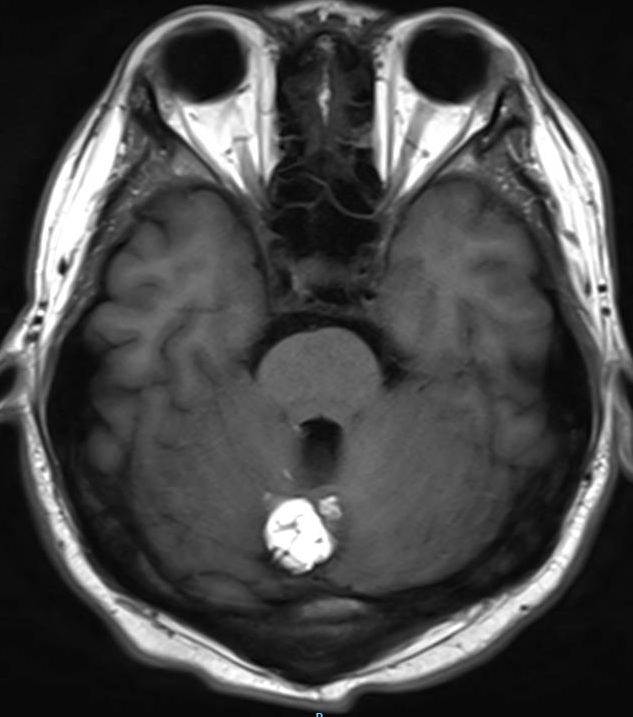

医生要求紧急做颅脑MRI,影像很快就传到了电脑上(图1-6)。医生解释,小脑蚓部占位考虑“脂肪瘤”,另有侧脑室旁白质脱髓鞘和左侧额顶叶皮质性脑炎的改变,“癫痫”可能为“继发性癫痫”。

图1 小脑蚓部占位T1WI